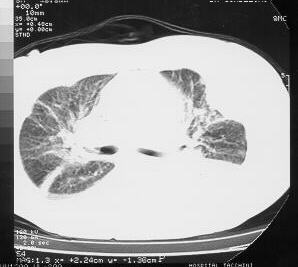

Chest CTs demonstrating the left thoracic wall mass, with intra-thoracic involvement, and costal arch destruction.